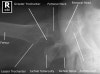

Hip Horizonatal Ray Lateral view

- Hip Lateral view

1) Alignment and Bones, Cartilage and joints

① 대퇴골 경부는 대퇴골에서 안쪽위로 30도 기울어져 있습니다.

② 어린이와 청소년의 경우에는 골간단(metaphysis)이 모두 골단(epiphysis)에 덮여 있는지 확인합니다.

③ SCFE(Slipped capital femoral epiphysis)에서는 대퇴골 몸통 끝의 중심이 뼈끝 중심에서 전방으로 이동되어 있는 것을 알 수 있습니다.

④ 고관절 탈구 환자의 경우 측면 영상에서 앞, 또는 뒤로 탈구되어 있는지 확인할 수 있습니다.

⑤ 대퇴골의 외면을 따라가면서 조사하고, 이어서 절구와 좌골(ischium)을 검사하여 탈구가 있다면 절구의 파편이 있는지 확인합니다.